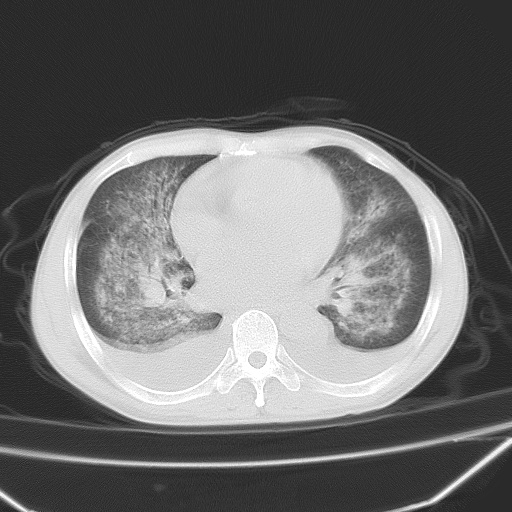

男、42岁、咯血3天。既往有甲亢、贫血、血尿蛋白尿史多年。血象:wbc:6.   中性粒:70.6%。

双肺堆成磨玻璃影,双测胸腔积液。考虑:肺水肿、间质性肺炎、真菌感染、ards、hiv感染、肺出血。

双肺野对称性磨玻璃影,分布于内中带,双侧胸水,患者有咯血。

1、间质性肺水肿;2、结合临床病史及实验室检查,考虑为肺出血肾炎综合征。    此病需与间质性炎症、粟粒性肺结核鉴别。

肺出血-肾炎综合征又称good-pasture综合征,属少见病,近几年国内有散在报告。此病原因未明,目前多数学者认为与自身免疫有关,即病人体内存在抗-gbm抗体,而病人肺毛细血管基底膜与肾小球基底膜有交叉反应性抗原,从而引起肺泡毛细血管基底膜和肾小球基底膜病变,导致肺出血及肾炎表现。血清抗-gbm抗体阳性,或组织活检见沿肾小球和肺泡基底膜有igg沉积,为本病的3个诊断依据。临床上有许多疾病同时表现为肺出血和肾炎,如系统性红斑狼疮、韦格肉芽肿和增殖性肾小球肾炎等,但这些疾病都不同时具备上述三方面的条件

双肺野广泛对称性磨玻璃影、实变影,以肺门为中心,主要分布于内中带,符合典型肺泡性肺水肿;伴双侧胸腔少量游离积液。结合患者既往病史且咯血就诊,支持多因素(尿毒症等)所致之肺水肿、肺出血、胸水;影像表现暂不考虑心源性水肿,且症状也不太符。需密切随诊结合临床治疗等进一步明确。